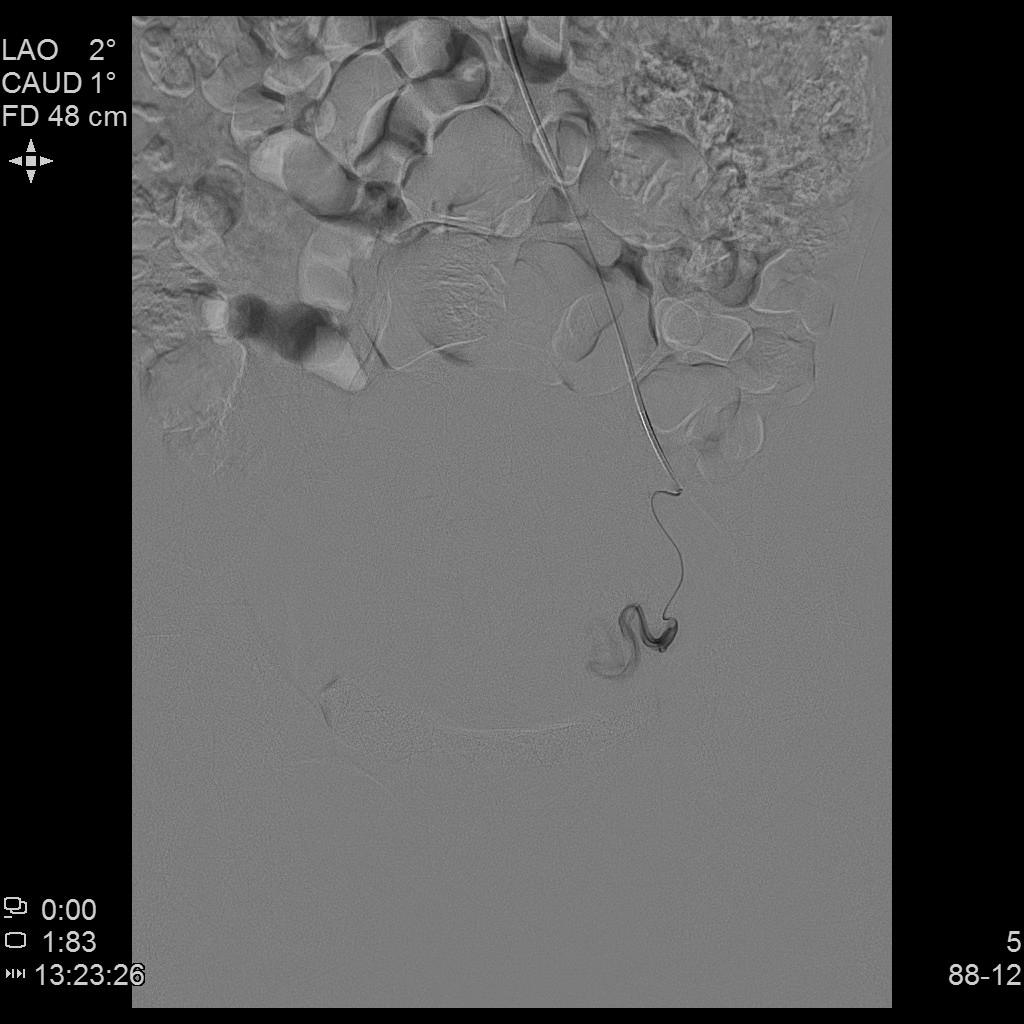

例4

中年女性,痛经10余年,近3个月明显加重。痛经达重度疼痛,严重影响生活质量。磁共振检查显示子宫前壁囊性病灶。临床诊断为囊性子宫腺肌症。

- 经左侧桡动脉穿刺置管,行腹主动脉造影显示双侧子宫动脉增粗、迂曲。

- 超选择插管右侧子宫动脉病灶供血动脉造影+栓塞治疗。

- 超选择插管左侧子宫动脉病灶供血动脉造影+栓塞治疗。

- 术后桡动脉压迫止血6小时,患者术后无需长时间卧床、下肢制动,舒适度明显提高,促进术后快速康复。